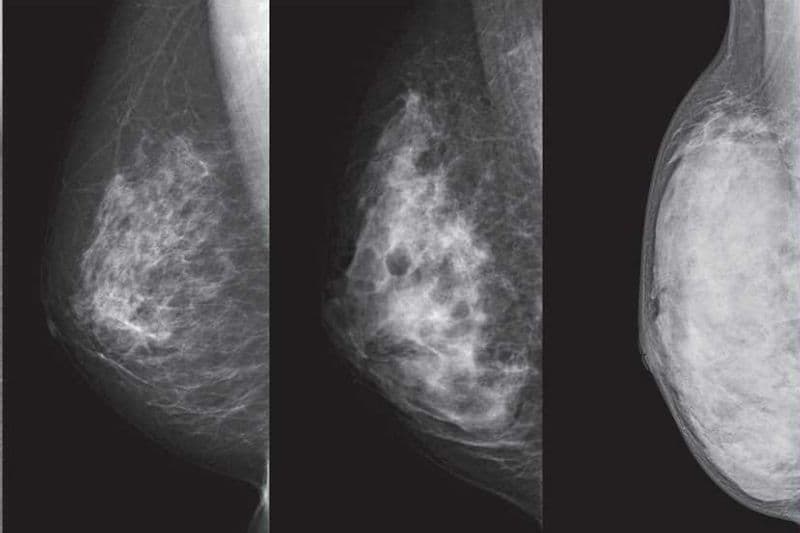

2.2. Hiệu quả với mô vú dày

Ở nhiều phụ nữ trẻ, mô tuyến vú thường dày hơn so với mô mỡ, khiến việc phát hiện bất thường bằng một số phương pháp khác gặp khó khăn. Trong những trường hợp này, siêu âm tầm soát ung thư vú có thể cung cấp hình ảnh rõ hơn vì sóng âm có khả năng xuyên qua mô tuyến dày đặc. Ở nhóm đối tượng này, độ nhạy của chụp nhũ ảnh có thể giảm đáng kể, từ khoảng 85% xuống còn khoảng 47,8% – 64,4%.Nhờ đó, siêu âm trở thành phương pháp bổ trợ quan trọng trong tầm soát ung thư vú, đặc biệt đối với phụ nữ có cấu trúc tuyến vú dày.

Một lợi ích quan trọng khác của siêu âm là khả năng phân biệt rõ giữa nang chứa dịch và khối u đặc trong tuyến vú. Trên hình ảnh siêu âm, các nang dịch thường có đặc điểm tròn đều, thành mỏng và chứa dịch bên trong nên thường là tổn thương lành tính. Ngược lại, các khối đặc với hình dạng không đều hoặc bờ không rõ có thể khiến bác sĩ nghi ngờ tổn thương ác tính và chỉ định thêm xét nghiệm chuyên sâu. Việc phân loại này giúp giảm thiểu các ca phẫu thuật không cần thiết đối với u lành.